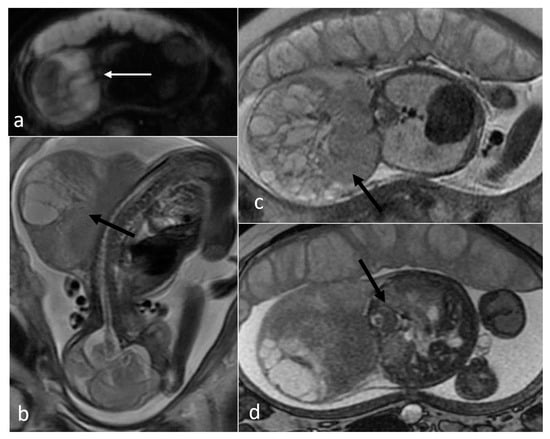

| Teratoma | sacrococcygeal | 25 | 268 [2.5–1145.165] | yes (13/17) [918–1661) | cystic (6) mixed (19) | yes 8/13 | yes (3/4) |

| head and neck | 13 | 176.1 [1.78–877.11] | yes (9/13) (796–1294) | solid (3) mixed (8) cystic (2) | yes (8/13) | yes (1) | |

| thorax and abdomen | 8 | 32 [1.49–134.98] | yes (3/6) | mixed (3) solid (3) cystic (2) | yes (4/5) | yes (1) | |